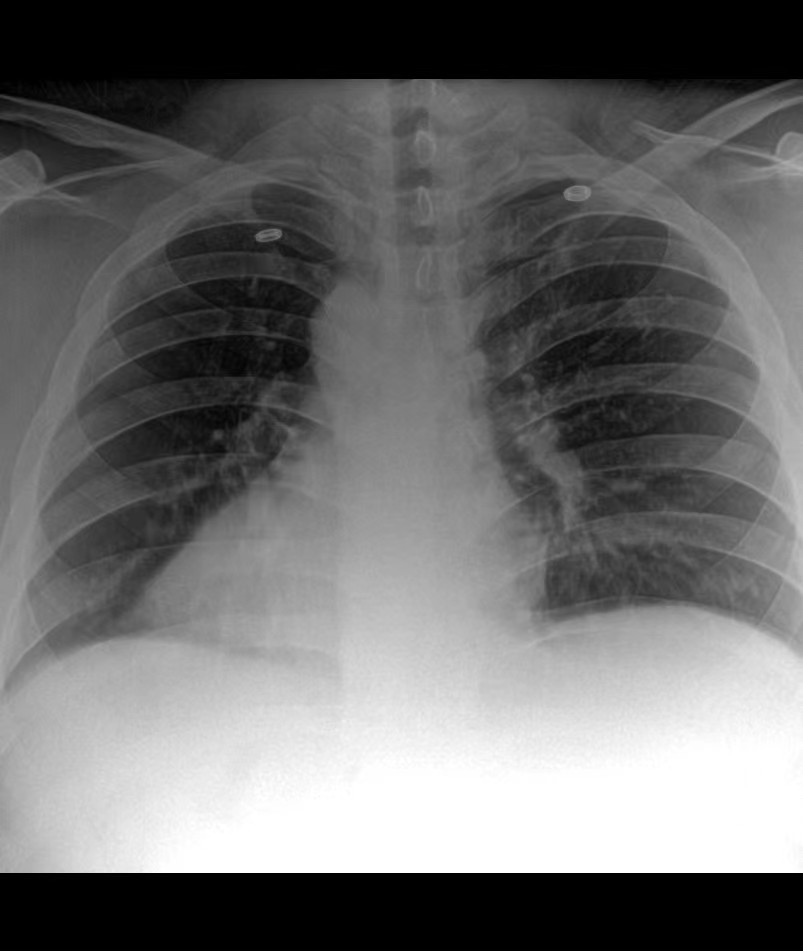

X光机剂量大了是发白还是发黑?是这样的,以拍摄胸片为例。如果是拍摄胸片时,X射线的剂量大,拍摄出的图像是会透过去的那种,也就是大家说的发黑。如果是拍摄胸片架,X射线的剂量小,X射线无法穿透拍摄的胸部,图像会发白。

简单给大家看下不同剂量下的胸片X线图像:

X光机成像效果图